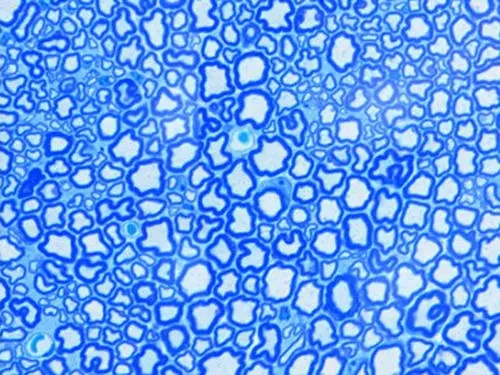

HE染色:苏木精 - 伊红染色法 ( hematoxylin-eosin staining ) ,简称HE染色法 ,石蜡切片技术里常用的染色法之一 。苏木精染液为碱性 ,主要使细胞核内的染色质与胞质内的核酸着紫蓝色 ;伊红为酸性染料 ,主要使细

HE染色:苏木精 - 伊红染色法 ( hematoxylin-eosin staining ) ,简称HE染色法 ,石蜡切片技术里常用的染色法之一 。苏木精染液为碱性 ,主要使细胞核内的染色质与胞质内的核酸着紫蓝色 ;伊红为酸性染料 ,主要使细胞质和细胞外基质中的成分着红色 。HE染色法是组织学、胚胎学、病理学教学与科研中最基本、使用最广泛的技术方法。

视网膜